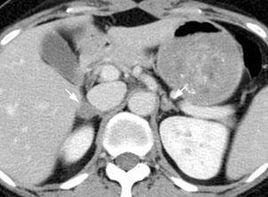

尿17-酮類醇水平高於同性別同年齡的正常者。尿中孕酮水平早期升高(這比尿17-KS的水平更為敏感,因孕酮是雄激素的前體),血17-羥孕酮水平升高是最敏感的指標,適用於兒童,染色體檢查正常。X線檢查會發現骨齡早化。側位尿道膀胱造影會顯示陰道,尿道和膀胱。CT掃描可見高度增生的腎上腺。尿道鏡可看清開口於尿道後壁的陰道,也能進入陰道並看到子宮。